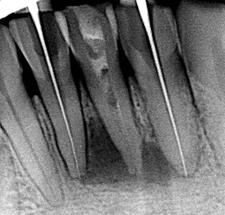

1) Внутриротовая контактная рентгенограмма.

Позволяет оценить степень резорбции костной ткани альвеолярного отростка (при снижении высоты на 1/3 и ниже проведение зубосохраняющей операции нецелесообразно). Состояние канала корня зуба, степень и качество его пломбирования. Наличие отломков инструментов в канале, наличие перфораций. Взаимоотношение кисты с корнями соседних зубов. Взаимоотношение корней соседних зубов с кистозной полостью может варьировать. Если корни вдаются в полость кисты, на рентгенограмме периодонтальная щель отсутствует вследствие рассасывания замыкательной пластинки лунок этих зубов. Если же периодонтальная щель определяется, то такие зубы только проецируются на область кисты, а на самом деле корни их располагаются в одной из стенок челюсти.

Рентгенологическая картина.

При рентгенологическом исследовании, поимо выявления околокорневой кисты в виде просветления округлой или овальной формы, окружающей корень зуба, важно оценить состояние самого причинного зуба, в частности степень разрушения связочного аппарата (периодонта), состояние канала корня, которое может характеризоваться следующими признаками:

- канал корня не запломбирован;

- канал корня заломбирован не до верхушки;

- канал корня запломбирован до верхушки с выведением пломбировочного материала;

- в канале корня находится обломок инструмента;

- перфорация стенки корня зуба;

- добавочное ответвление от основного канала;

- перелом корня зуба.